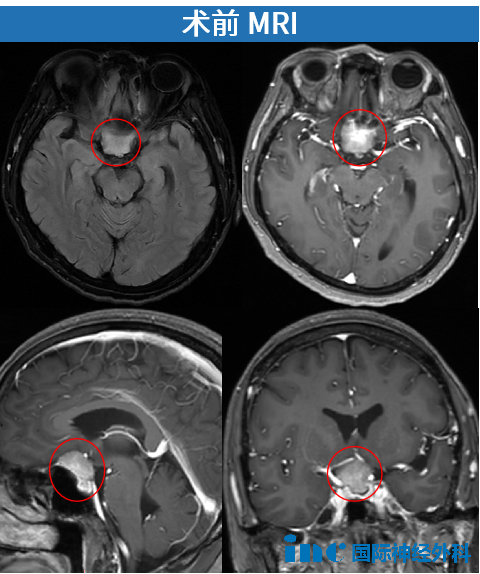

2024年12月17日,远在异国的陈女士因面瘫、视物模糊被确诊为鞍区脑膜瘤。病情不等人——短短4天后,她已紧急飞回国内。进一步检查显示,肿瘤匍匐于鞍底,约2.6cm×2.5cm。

由于这个肿瘤位于前颅底,从两条视神经之间生长,并随着其增大逐渐压迫了视神经。此外,肿瘤的位置十分险要,还波及到了垂体及垂体柄。

这不仅仅是肿瘤的问题,肿瘤还会压迫供应视神经和视交叉的血管,损伤视神经的血液供应,这很容易导致肿瘤和视神经的梗塞,患者可能会完全失明。

巴教授在为陈女士评估时表示:有时候医生担心失明的风险,会让患者接受伽马刀治疗,但这通常会使情况更糟,因为伽马刀也可能引起失明,并且会使后续的手术变得更加复杂。肿瘤和视神经会变得非常粘连,这会使手术更加困难。因此,伽马刀对她来说并不是一个好的选择。